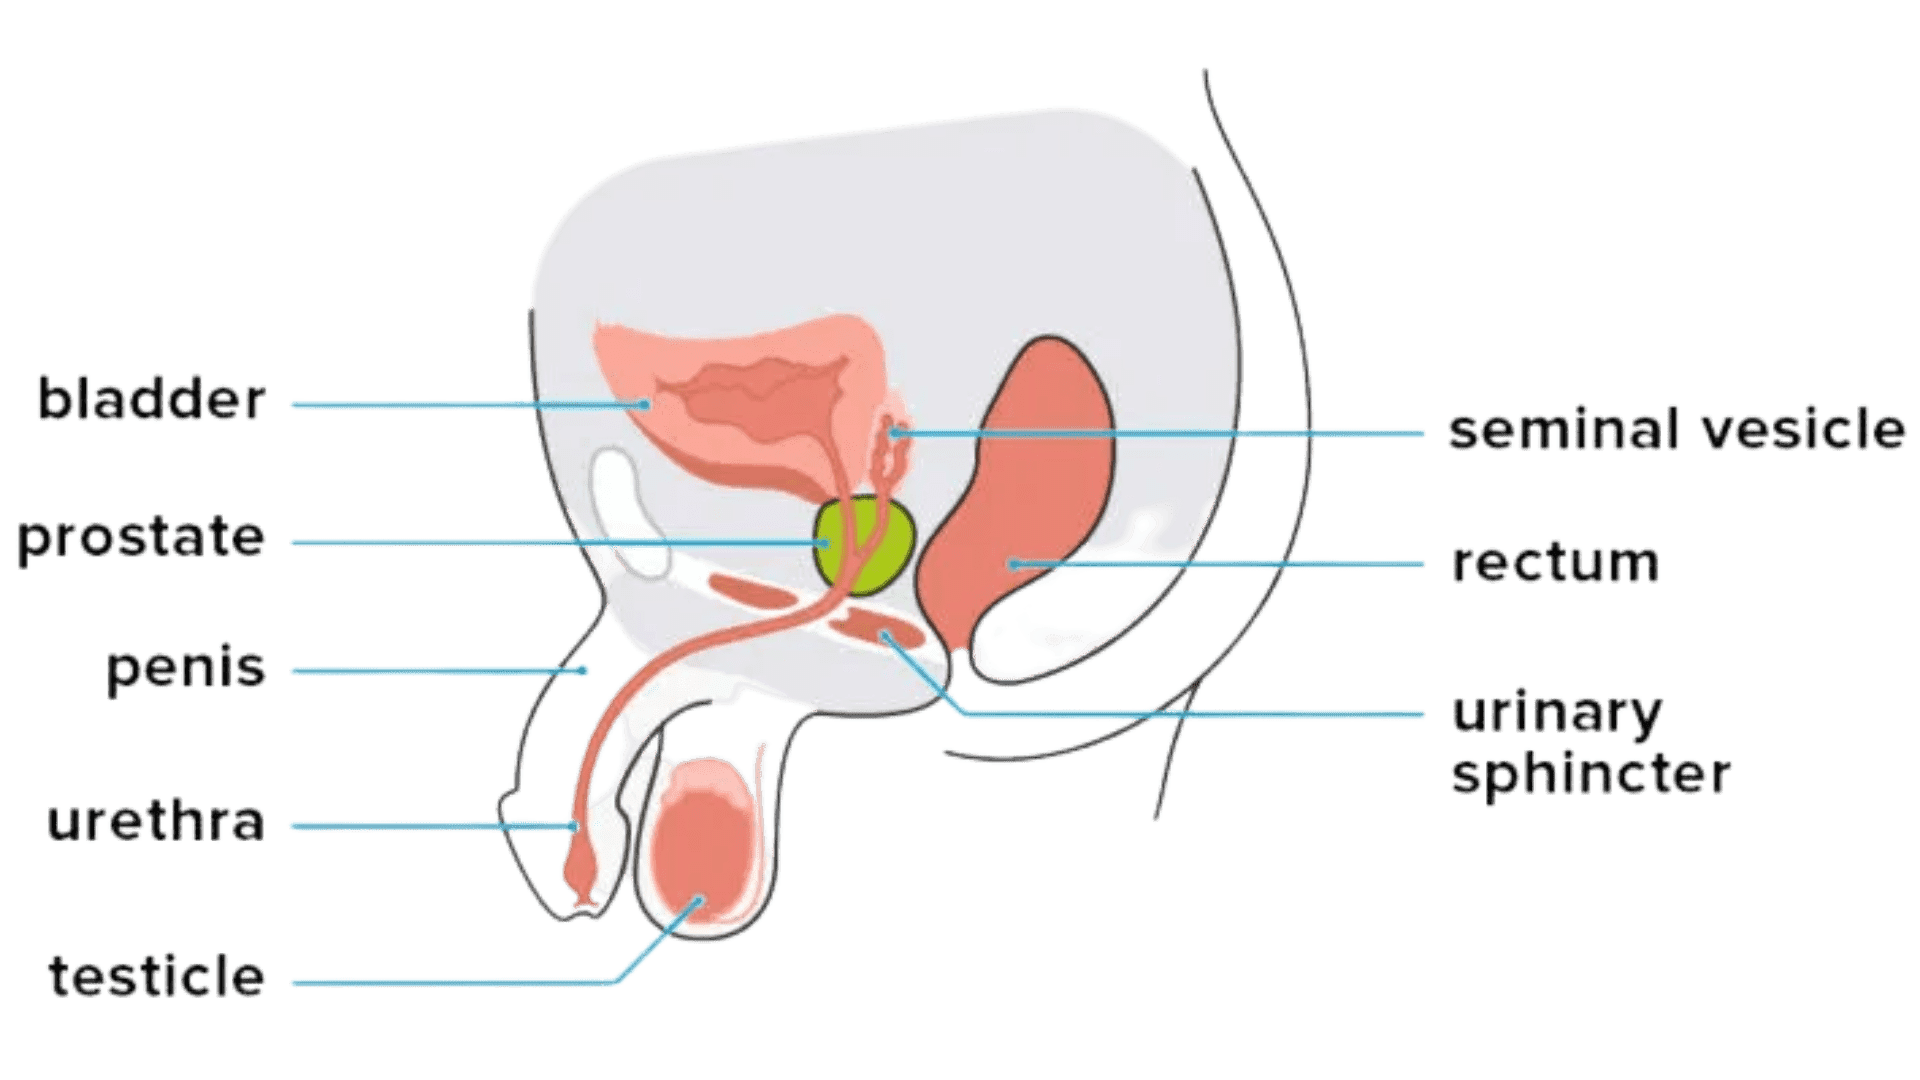

Diagnostic tests benign prostatic hyperplasia (bph) several tests help to confirm benign prostatic hyperplasia (bph) diagnosis:

Diagnostic tests benign prostatic hyperplasia (bph) several tests help to confirm benign prostatic hyperplasia (bph) diagnosis:

Diagnostic tests benign prostatic hyperplasia (bph) several tests help to confirm benign prostatic hyperplasia (bph) diagnosis:

Diagnostic tests benign prostatic hyperplasia (bph) several tests help to confirm benign prostatic hyperplasia (bph) diagnosis:

Diagnostic tests benign prostatic hyperplasia (bph) several tests help to confirm benign prostatic hyperplasia (bph) diagnosis:

Diagnostic tests benign prostatic hyperplasia (bph) several tests help to confirm benign prostatic hyperplasia (bph) diagnosis:

Diagnostic tests benign prostatic hyperplasia (bph) several tests help to confirm benign prostatic hyperplasia (bph) diagnosis:

Diagnostic tests benign prostatic hyperplasia (bph) several tests help to confirm benign prostatic hyperplasia (bph) diagnosis:

Diagnostic tests benign prostatic hyperplasia (bph) several tests help to confirm benign prostatic hyperplasia (bph) diagnosis:

Diagnostic tests benign prostatic hyperplasia (bph) several tests help to confirm benign prostatic hyperplasia (bph) diagnosis:

Diagnostic tests benign prostatic hyperplasia (bph) several tests help to confirm benign prostatic hyperplasia (bph) diagnosis: